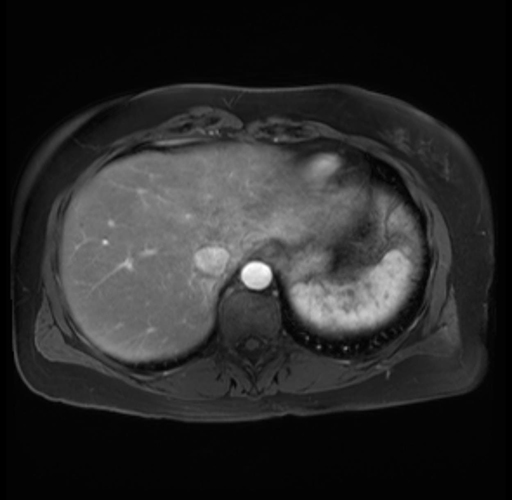

Imaging Analysis

Look through the patient's CT scan to identify any areas of concern for the necessary procedure.

Based on your CT findings, which issue(s) are present and would give reason for "planned slowing down moment(s)" in this case?

Considering a standard distal pancreatectomy procedure, what step(s) of the operation would you do differently in this case?